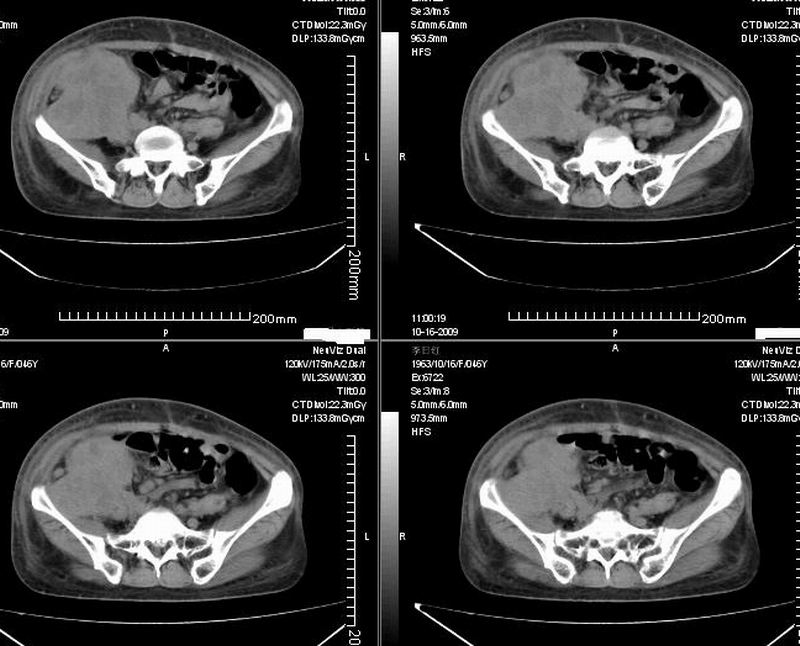

女:46y:一年前宫颈癌术后,现右下腹抚及肿块。

考虑宫颈癌术后复发周边侵犯/右中下腹及双侧腹股沟淋巴结转移。

考虑宫颈癌术后复发周边侵犯并右中下腹转移灶及双侧腹股沟淋巴结转移。